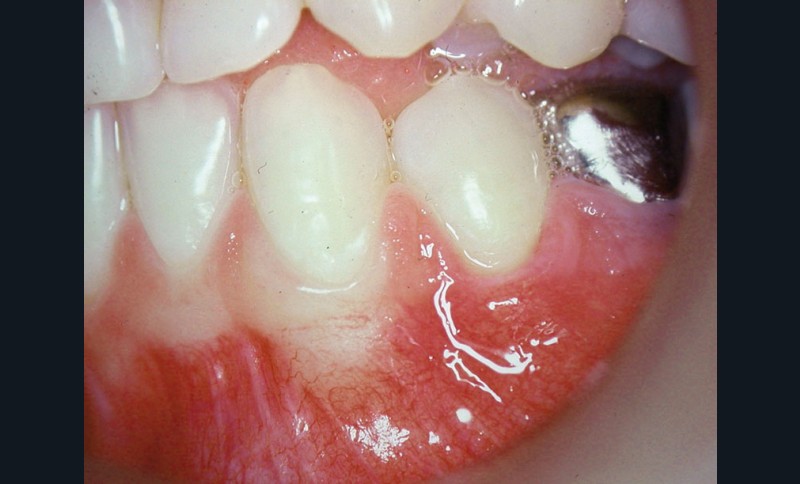

Cas clinique 1

Dans ce premier cas, la présence d’un complexe muco-gingival inadéquat (fig. 1) est observée sur une canine et une prémolaire.

Cette absence de gencive attachée peut prédisposer à la formation d’une récession gingivale. Une greffe épithélio-conjonctive est réalisée. Elle permet d’obtenir un lambeau de gencive attachée kératinisée stable (fig. 2).